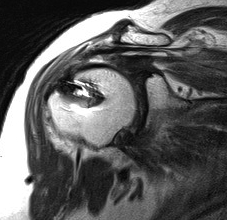

Massive tear

1. > 5cm

- retracted to humerus / glenoid margin

2. At least 2 complete tendons

- lose SS / IS or SS / SC